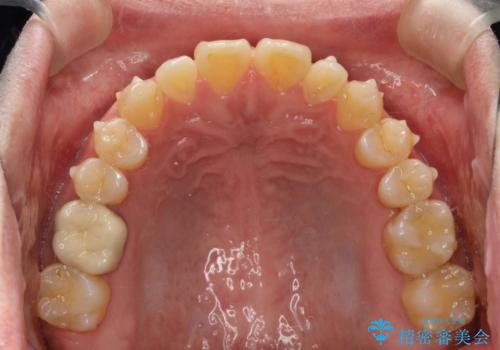

前歯の真ん中の隙間を閉じたい インビザラインによる目立たない矯正

- 上顎の正中の隙間が気になるとのことで来院されました。

下の歯と歯の間をわずかに削り、スペースを作り、正中の隙間を閉じる計画としました。

装置はインビザラインにて行いました。

インビザラインで目立たずに矯正治療を行うことができました。

使用時間を守っていただけたので、比較的スムーズに矯正を終了することができました。